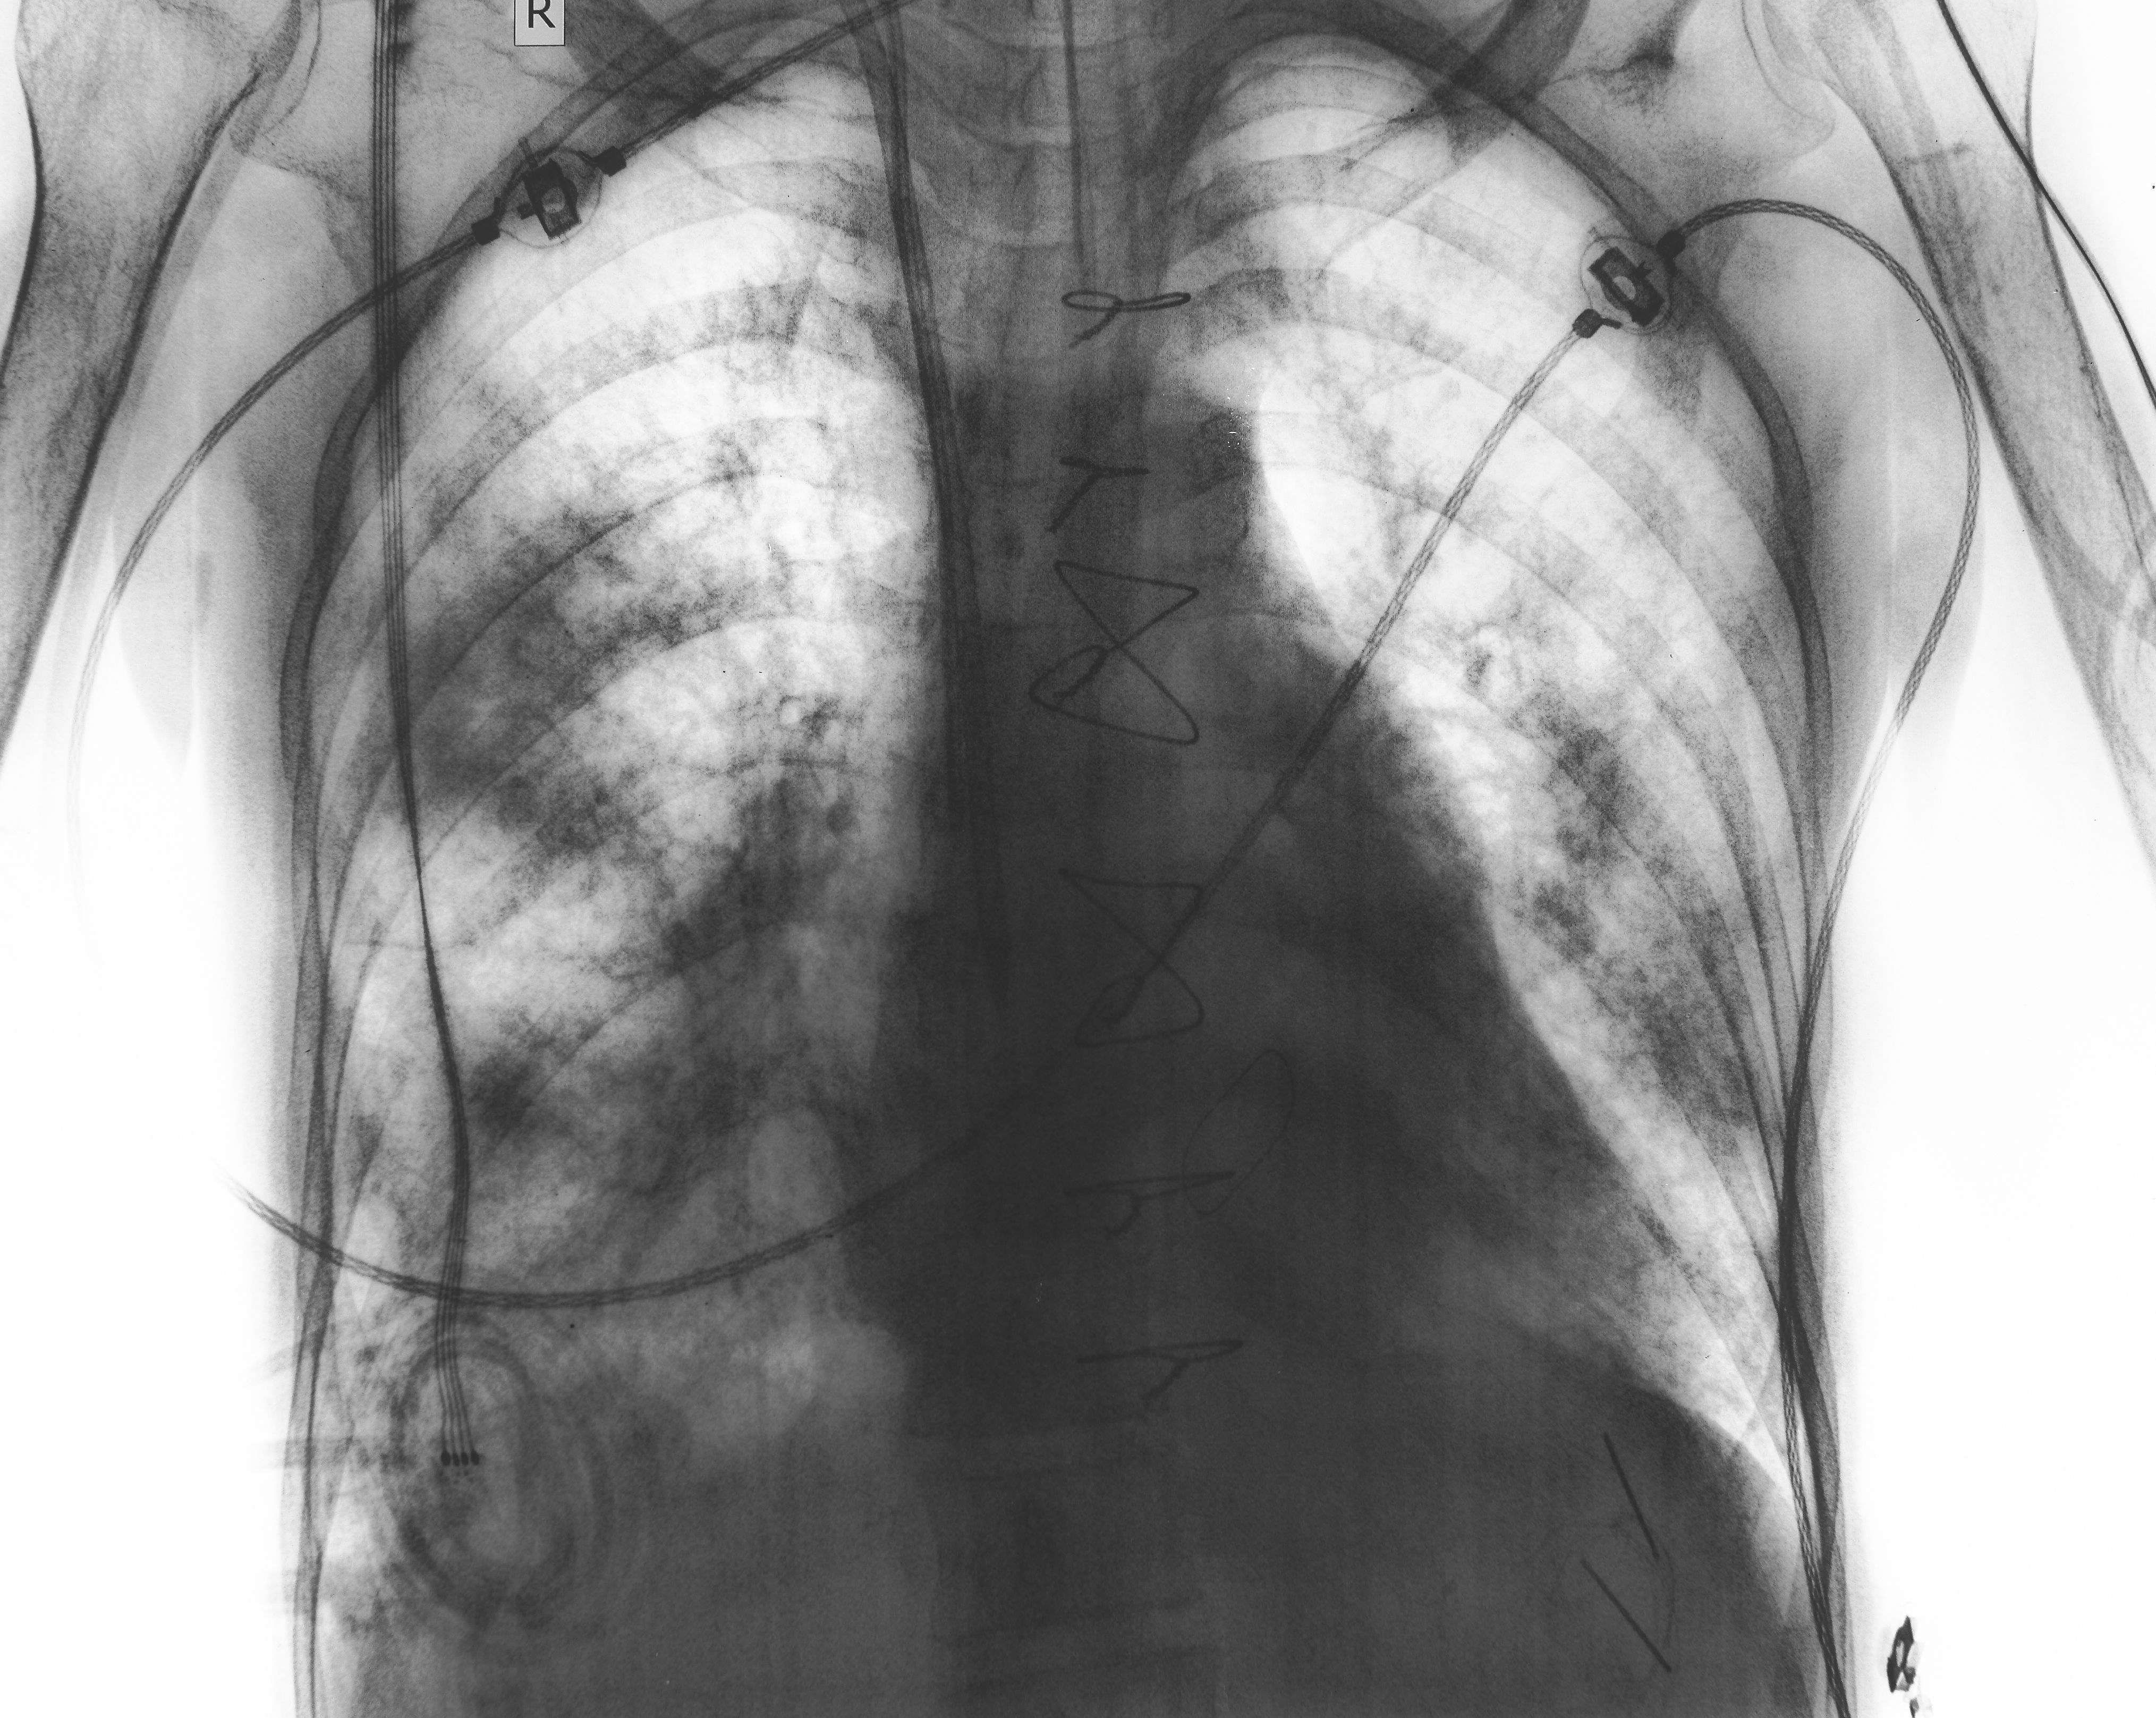

2. Paru-paru mengempis (pneumothorax)

COPD boleh merosakkan tisu paru-paru. Jika terdapat udara bocor keluar dan masuk ke dalam ruang antara paru-paru dan dada, paru-paru akan mengempis seperti belon yang dibuang angin. Simptom yang dialami adalah nafas pendek secara tiba-tiba, sakit atau dada terasa sempit dan batuk.

Rawatannya mungkin hanya memberikan oksigen atau pembedahan.